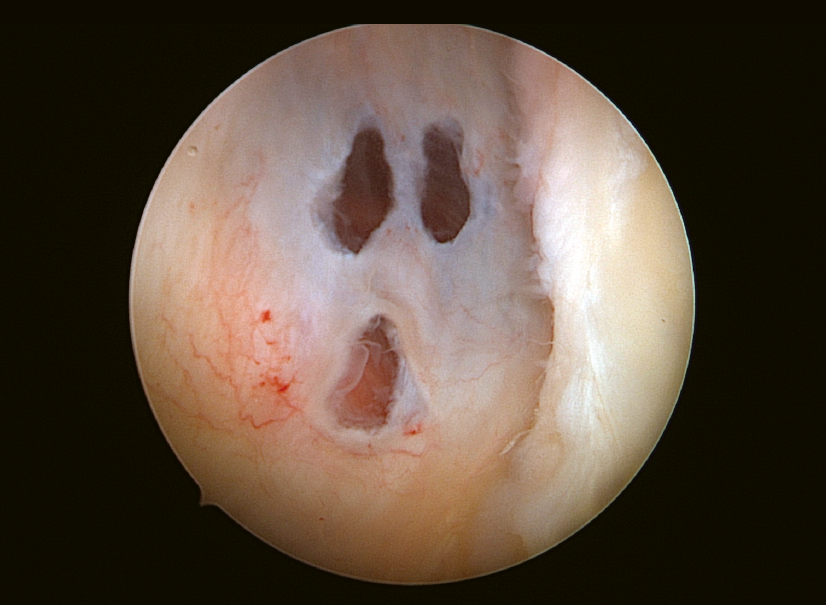

Después de realizar el abordaje artroscópico posterior habitual de un hombro izquierdo con algunas dificultades, colocamos la óptica en el portal anterosuperior para evaluar el labrum posterior y pudimos ver cómo la cápsula posterior había sido perforada en 3 lugares, ofreciendo una gran similitud con el aspecto del fantasma de Scream.